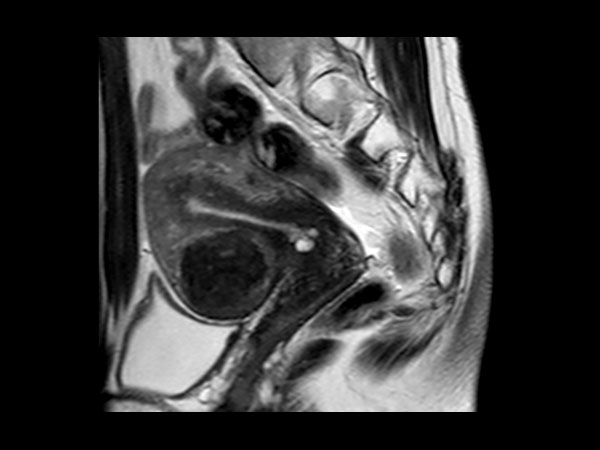

Female Pelvis

Toyonaka Hospital, Japan